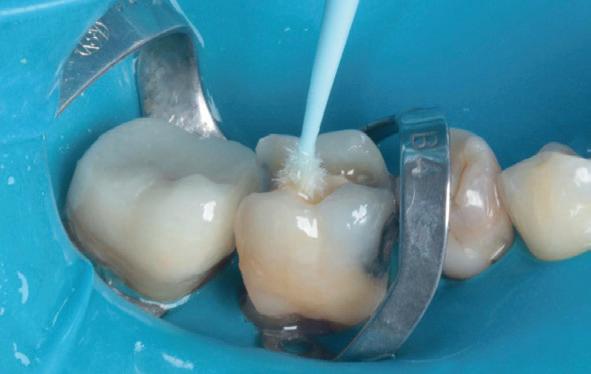

Deze 51-jarige vrouw werd verwezen omwille van pijnklachten met de vraag of een wortelkanaalbehandeling nog mogelijk was, of dat er eerder naar extractie gekeken moest worden (foto 7). De tand testte nog vitaal tijdens de consultatie dus ik besloot om eerst de vulling te verwijderen. Het bleek een typische “cracked tooth” (foto 8-9). Ik besloot om de tand te voorzien van een adhesieve stompopbouw (foto 10). En bij de opvolging zes maanden later (foto 11) was de patiënt al die tijd klachtenvrij en kreeg de tandarts groen licht om verder te gaan met een indirecte restauratie. Geen wortelkanaalbehandeling en al zeker geen extractie nodig.

Elke tandarts kent het. Je hebt een endostart uitgevoerd, maar een week later komt de patiënt weer terug met klachten. Het ging de goede kant op, maar na een paar dagen kwam de pijn toch weer opzetten. ‘’Raar, ik weet toch zeker dat ik alle kanalen netjes heb gereinigd’’, denk je dan bij jezelf. Het is een soort gemeengoed geworden, om de patiënt dan tussendoor te laten komen zodat de kanalen weer gedesinfecteerd kunnen worden met natriumhypochloriet. Maar is dat wel doeltreffend? Waarom zijn die bacteriën zo snel weer van betekenis geworden? Graag leg ik kort uit hoe je deze situatie kunt voorkomen aan de hand van een eenvoudige casus uit de praktijk.

Een 58-jarige patiënt was naar onze praktijk verwezen door zijn eigen tandarts. Hij had pijn en een flinke zwelling aan element 35. Zijn tandarts had een nette endodontische opening gemaakt en het element ontdaan van al het geïnfecteerde en/of necrotische pulpaweefsel en het kanaal uitvoerig gedesinfecteerd.

Aanvankelijk ging het goed, maar na een paar dagen kwam de patiënt toch weer terug met een flinke zwelling. Ondanks herhaalde behandelingen kwam de klacht net zo hard weer terug. Dit proces heeft zich wel zes keer herhaald, zonder resultaat.

Wat direct opviel aan de meegestuurde röntgenfoto was de matige coronale restauratie. De lekkende vulling zou het pijnlijke proces dat meneer heeft doorgemaakt verklaren. Bij het spoelen van het wortelkanaalstelsel wordt dan weliswaar veel gedesinfecteerd, maar binnen de kortste keren stromen de bacteriën en het substraat via de lekkage onder de vulling doodleuk weer naar binnen!

Naast de matige restauratie kon ik verder geen open apex, verticale fractuur of een andere oorzaak ontdekken, waardoor de bacteriën in het element zich in rap tempo konden vermenigvuldigen.

Om te voorkomen dat er niet wéér een infectie plaatsvindt, heb ik tijdens het eerste consult niet alleen het wortelkanaalstelsel gedesinfecteerd, maar ook direct de coronale restauratie vervangen.